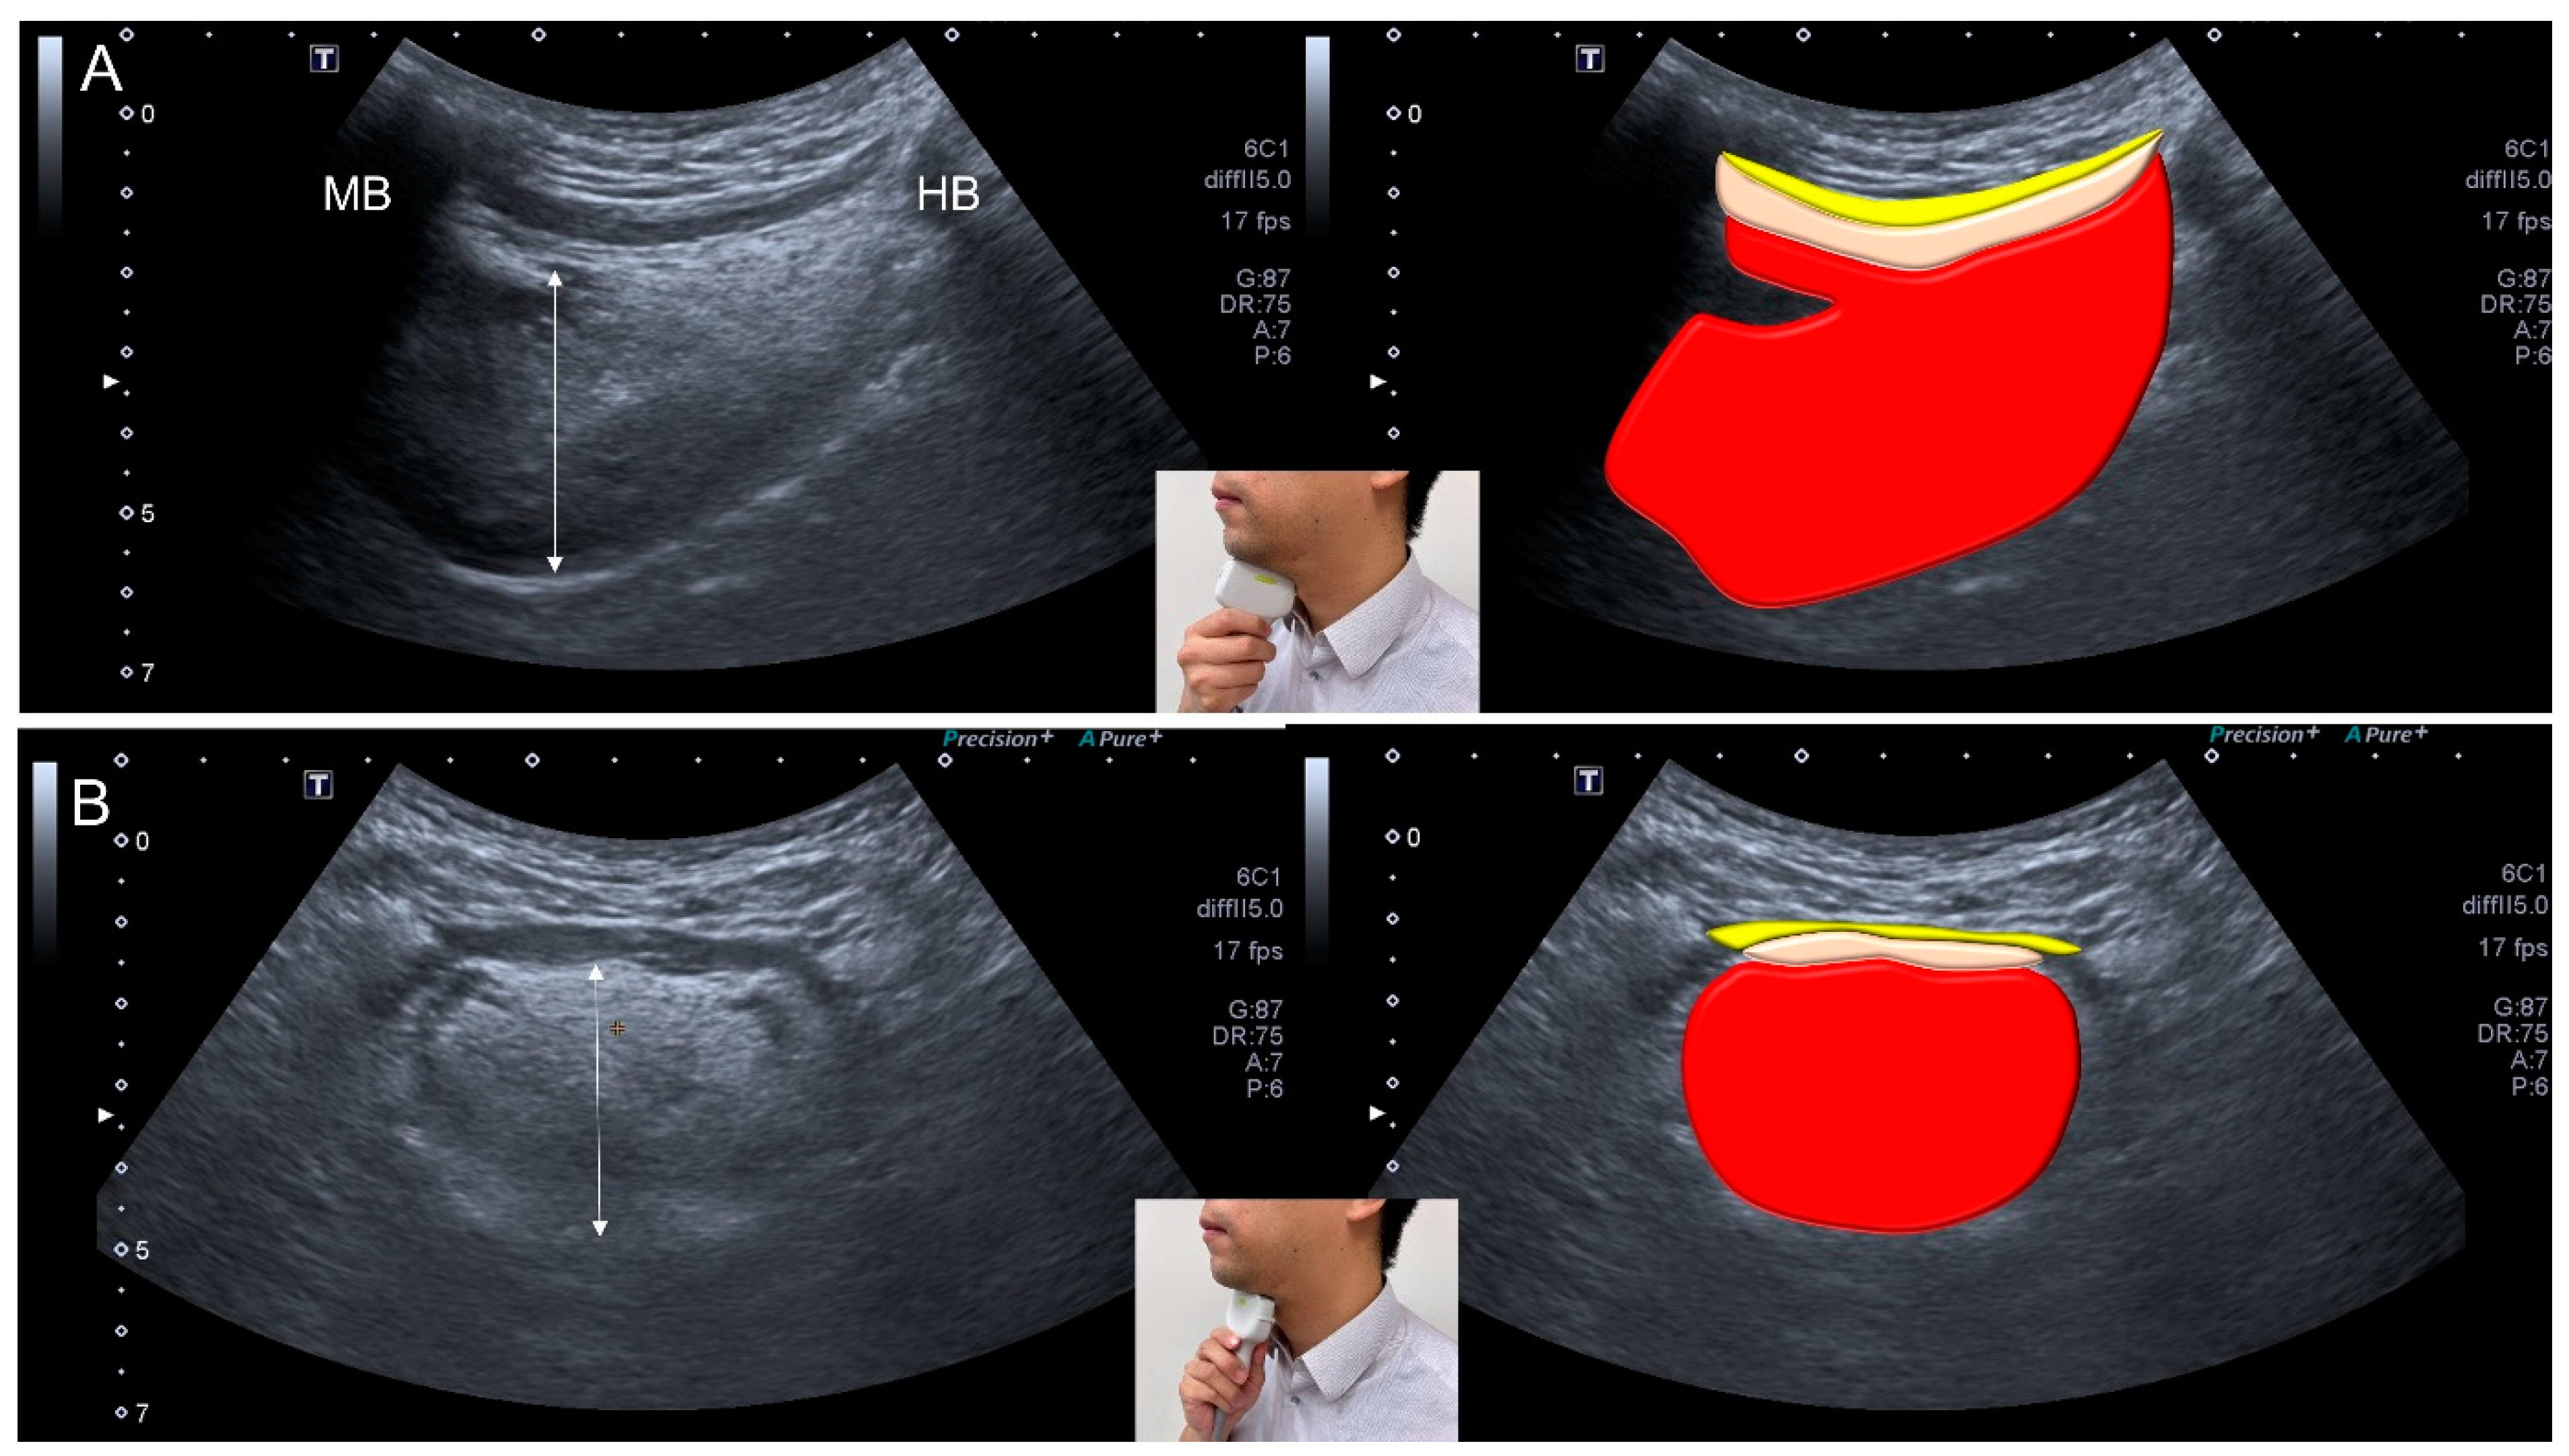

3.9. Ultrasonography

- Ogawa, N.; Mori, T.; Fujishima, I.; Wakabayashi, H.; Itoda, M.; Kunieda, K.; Shigematsu, T.; Nishioka, S.; Tohara, H.; Yamada, M.; et al. Ultrasonography to Measure Swallowing Muscle Mass and Quality in Older Patients With Sarcopenic Dysphagia. J. Am. Med. Dir. Assoc. 2018, 19, 516–522. [Google Scholar] [CrossRef]

- Mori, T.; Wakabayashi, H.; Ogawa, N.; Fujishima, I.; Oshima, F.; Itoda, M.; Kunieda, K.; Shigematsu, T.; Nishioka, S.; Tohara, H.; et al. The Mass of Geniohyoid Muscle Is Associated with Maximum Tongue Pressure and Tongue Area in Patients with Sarcopenic Dysphagia. J. Nutr. Health Aging 2021, 25, 356–360. [Google Scholar] [CrossRef] [PubMed]

- Ogawa, N.; Wakabayashi, H.; Mori, T.; Fujishima, I.; Oshima, F.; Itoda, M.; Kunieda, K.; Shigematsu, T.; Nishioka, S.; Tohara, H.; et al. Digastric muscle mass and intensity in older patients with sarcopenic dysphagia by ultrasonography. Geriatr. Gerontol. Int. 2021, 21, 14–19. [Google Scholar] [CrossRef] [PubMed]

| Ultrasonography | <1536 mm2 for the cross-sectional area of the tongue muscle <75.1 mm2 for the cross-sectional area of the digastric muscle |